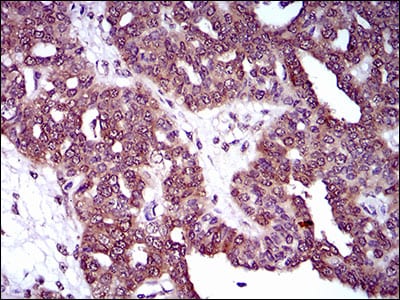

分类: 科研抗体货号: 30521别名: MRP4; MOATB; MOAT-B; EST170205应用: IHC,FCM反应种属: Human

分类: 科研抗体货号: 30526别名: MRP4; MOATB; MOAT-B; EST170205应用: IHC,FCM反应种属: Human